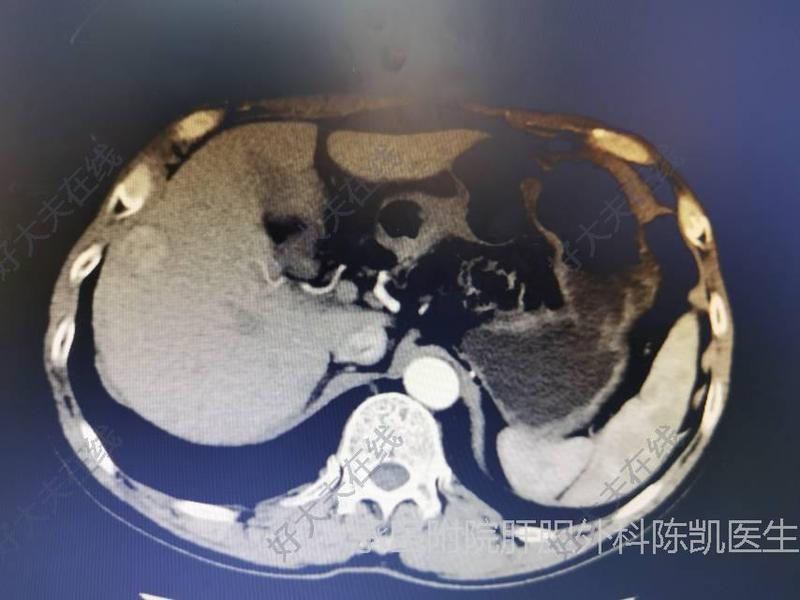

治療前患者,男,主因發(fā)現(xiàn)肝臟占位8天入院。既往有乙肝病史8個(gè)月,口服恩替卡韋1片日一次抗病毒治療。查體無(wú)特殊。術(shù)前肝膽脾強(qiáng)化CT提示:肝內(nèi)實(shí)性占位,考慮惡性。初步診斷:肝占位性病變。決定行肝癌切除術(shù)。治療中術(shù)中探查發(fā)現(xiàn):肝臟呈彌漫性結(jié)節(jié)樣改變,淡黃色腹水少量。肝5段與8段交界處可見(jiàn)一直徑約2.5厘米腫瘤,突出肝表面,界清,色灰白。術(shù)中診斷:肝癌。遂決定行肝癌切除術(shù)。距腫瘤邊緣2厘米切開(kāi)肝實(shí)質(zhì),依次向深側(cè)分離肝實(shí)質(zhì),采用吳金術(shù)教授提出的“四邊法”。直到完整切除肝腫瘤。治療方案選擇:肝癌的手術(shù)切除,有解剖性肝切除和非解剖性肝切除。哪一種更好存在一定的爭(zhēng)議。前者認(rèn)為肝癌通過(guò)門(mén)靜脈轉(zhuǎn)移,因此需切除門(mén)靜脈流域的肝段。后者的理論基礎(chǔ)是肝癌不按段生長(zhǎng),可能跨界長(zhǎng),要保證足夠腫瘤切緣才走意義。本病例,因患者肝硬化重,肝臟小,若行解剖性肝5段8段切除,術(shù)后可能出現(xiàn)肝衰竭,頑固性腹水,術(shù)后肝創(chuàng)面滲血等,并發(fā)癥多。因此,該患者采用不規(guī)則性肝切除,保證足夠切緣的肝切除,切緣不少于1厘米,保證病人的安全。治療后治療后0天術(shù)后應(yīng)用抗生素預(yù)防感染,護(hù)肝,適當(dāng)補(bǔ)液治療。目前病人已進(jìn)食,離床活動(dòng),恢復(fù)良好。腹腔引流少量淡血性液體。